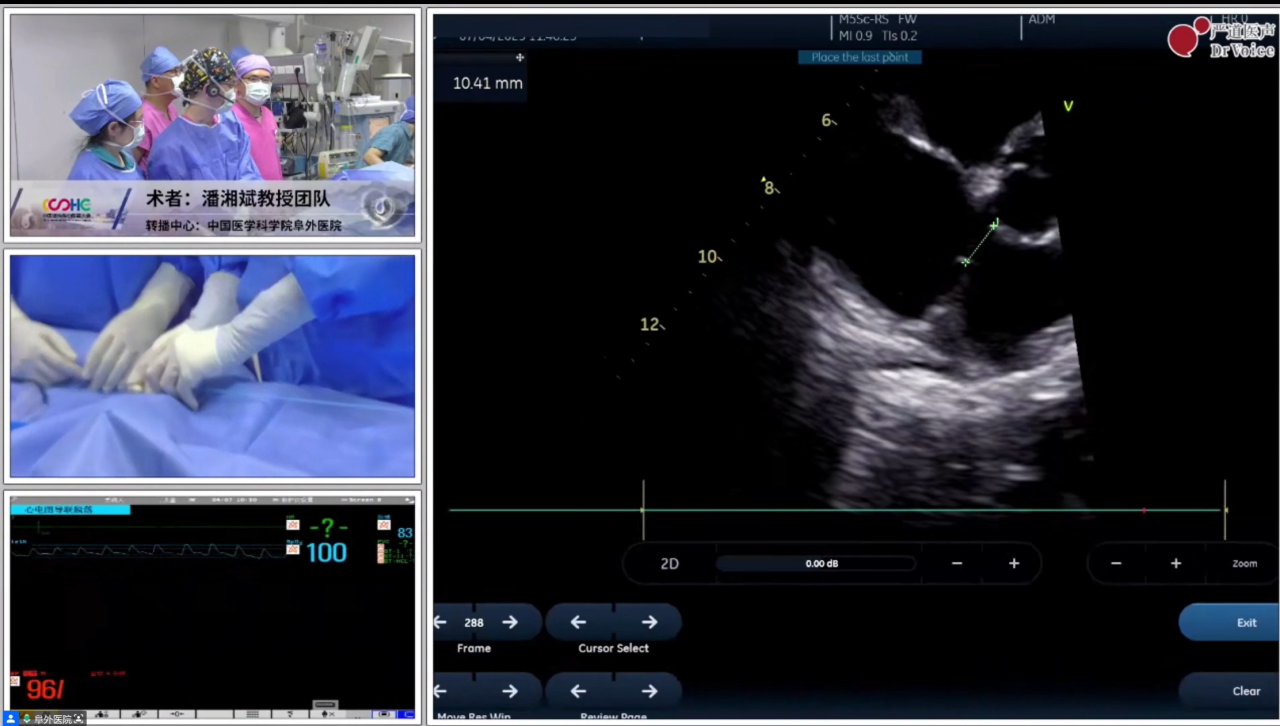

实战示教:中国医学科学院阜外医院结构性心脏病团队——两例单纯TTE引导下可降解PFO封堵术

左:第一例手术录播、右:第二例手术直播

第一例患者较年轻,有脑梗史,反复头痛数年,经食道发泡试验阳性,提示存在PFO。第二例患者39岁,偏头痛10余年,头颅核磁提示多发缺血灶,食道超声证实PFO,宽约2.4 mm、长约8 mm。两例患者均具备封堵指征,结合患者意愿,经术前充分检查后拟行单纯TTE引导下可降解PFO封堵,分别植入对称型24 mm*24 mm可降解PFO封堵器、对称型24 mm*24 mm可降解PFO封堵器。

为减少大鞘在心房内停留时间,可提前装载封堵器。两例手术均在单纯超声指导下开展,第二例患者术中通过导管配合超声导丝法顺利过隔,第一例患者经导管导丝探查法尝试过隔未果后,改用鞘管配合导丝法。术中所采用的PannaWire超声专用导丝为两例手术的新利器,其头端呈梭型,超声很容易探测,具有较佳的指向性,既降低了过隔难度,又提升了操作安全性。对于第一例患者,经超声确认导丝头端位于卵圆窝附近后,保持鞘管头端垂直指向房间隔方向缓慢推送,待导丝头端影像消失即提示鞘管已成功贴靠卵圆窝,后在其支撑下,导丝顺利过隔,建立股静脉至左心房的导丝轨道。

完成导丝轨道建立后,置入输送鞘。封堵器经鞘顺利送入左房后,在超声引导下先释放左盘面,通过牵拉成型线使其由“灯笼状”变为“盘状”,再回撤钢缆,使左盘紧贴房间隔。待右盘面释放后牵拉成型线,若超声下观察到右盘随房间隔摆动,且双盘贴合于间隔、形态合适,即开始锁定。成型锁定后,超声下双盘面紧紧扣合在房间隔两侧,形态良好,且轻轻牵拉钢缆,双盘相对位置保持不变,依然紧贴合房间隔,判定锁定成功。